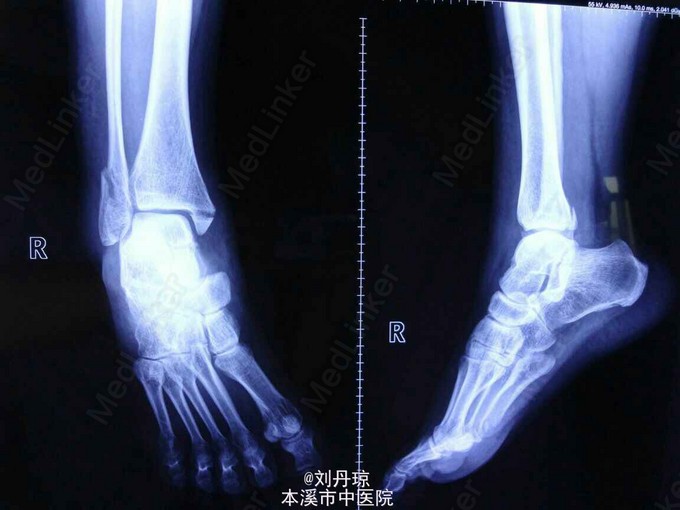

患者女,40岁。 主诉:右踝关节刺痛,活动受限6小时。 病史:患者6小时前走路时不慎扭伤右踝,伤后患者来我院门诊,门诊医师以‘’右踝关节骨折‘’诊断收入院,现患者无发热,饮食正常,大小便可。既往健康。

查体:患者生命体征正常,踝关节肿胀、畸形,内、外、后踝压痛阳性,有骨擦感,右踝关节功能障碍。 辅查:旋后外旋型踝关节骨折脱位

诊断:踝关节骨折脱位 ( 旋后外旋型 ) 治疗:切开复位内固定